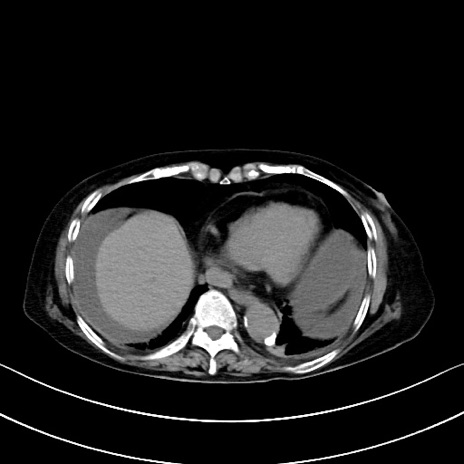

横断像